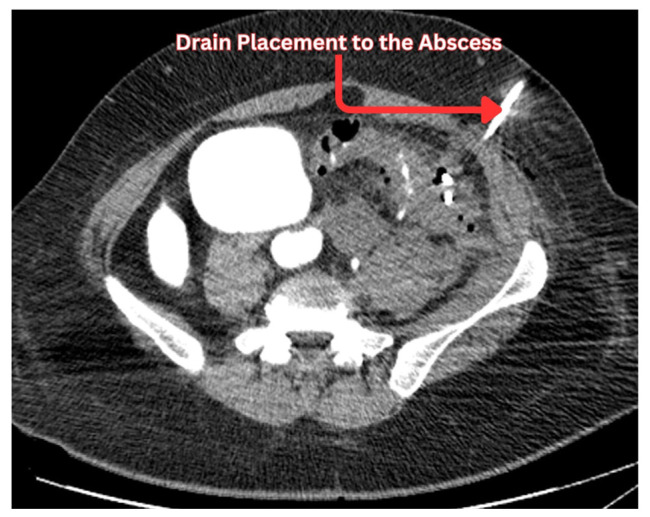

憩室囊的炎症称为急性憩室炎,有时可导致脓肿形成。经皮引流是治疗憩室脓肿的常规方法。作为一种用于从脓肿中清除大量感染液体的微创手术,经皮引流术成为一种有吸引力的选择。从历史上看,手术切除脓肿导致多次住院治疗,增加了医疗资源的负担。随着放射学技术的进步,ct引导下经皮引流憩室脓肿确保了患者满意度的提高和医疗成本的降低。选择手术或经皮引流憩室脓肿仍然是一个问题的争论医师。经皮引流手术的结果在文献中是分散的。在憩室脓肿的治疗过程中,熟悉经皮引流或结肠切除术的选择标准是很重要的。经皮引流可以防止紧急结肠切除术,但它并不总是一个无风险的程序。可引起持续性脓肿、新发脓肿、腹壁脓肿、腹膜炎等并发症。因此,医生必须提前做好准备,通过选择合适的人群进行手术,并确保良好的导管护理,包括重新调整导管,冲洗导管和升级导管尺寸,以预防这些并发症。医生不仅要预防这些并发症,还要有效地治疗它们。本文旨在从临床角度总结经皮引流憩室脓肿的重要结果及其进一步处理。

The inflammation of the diverticular pouch is called acute diverticulitis which can result in abscess formations sometimes. Percutaneous drainage is routinely considered for the management of diverticular abscesses. Being a minimally invasive procedure employed for the removal of large collections of infected fluid from the abscesses, percutaneous drainage emerged as an appealing option. Historically, surgical removal of the abscesses has resulted in multiple hospitalizations and an increased burden on healthcare resources. With the advancement in radiological techniques, CT-guided percutaneous drainage of diverticular abscesses ensured enhanced patient satisfaction and reduced healthcare costs. The choice between surgery or percutaneous drainage of diverticular abscess remains a matter of debate among physicians. The outcomes of percutaneous drainage procedures are scattered across the literature. It is important to be familiar with the criteria regarding the choice of percutaneous drainage or colectomy during the management of diverticular abscesses. Percutaneous drainage can prevent emergent colectomy but it is not always a risk-free procedure. It can bring complications including persistent abscess, new onset abscess, abdominal wall abscess, and peritonitis. Therefore, a physician must prepare in advance to prevent these complications by selecting the right population for the procedure and ensuring good catheter care which involves readjusting the catheter, flushing the catheter and upgrading the size of the catheter. A physician not only prevents these complications but also effectively treats them. This review paper aims to summarize the important outcomes of percutaneous drainage of diverticular abscesses and their further management from a clinical standpoint.